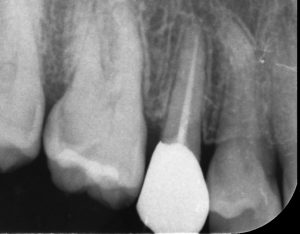

被せ物の装着

茂原市の患者さんは根管治療後、矯正治療を行いました。根管治療から2年半後、矯正治療が終わりましたので最終的な被せ物を装着しました。

ジルコニアクラウン(自費診療)です。強度がある、汚れがつきにくい、見た目が自然というのがジルコニアの特徴です。茂原市の患者さんも歯を残すことができ大変喜んでいらっしゃいました。現在も定期検診のため茂原市から数ヶ月に一度来院くださっています。